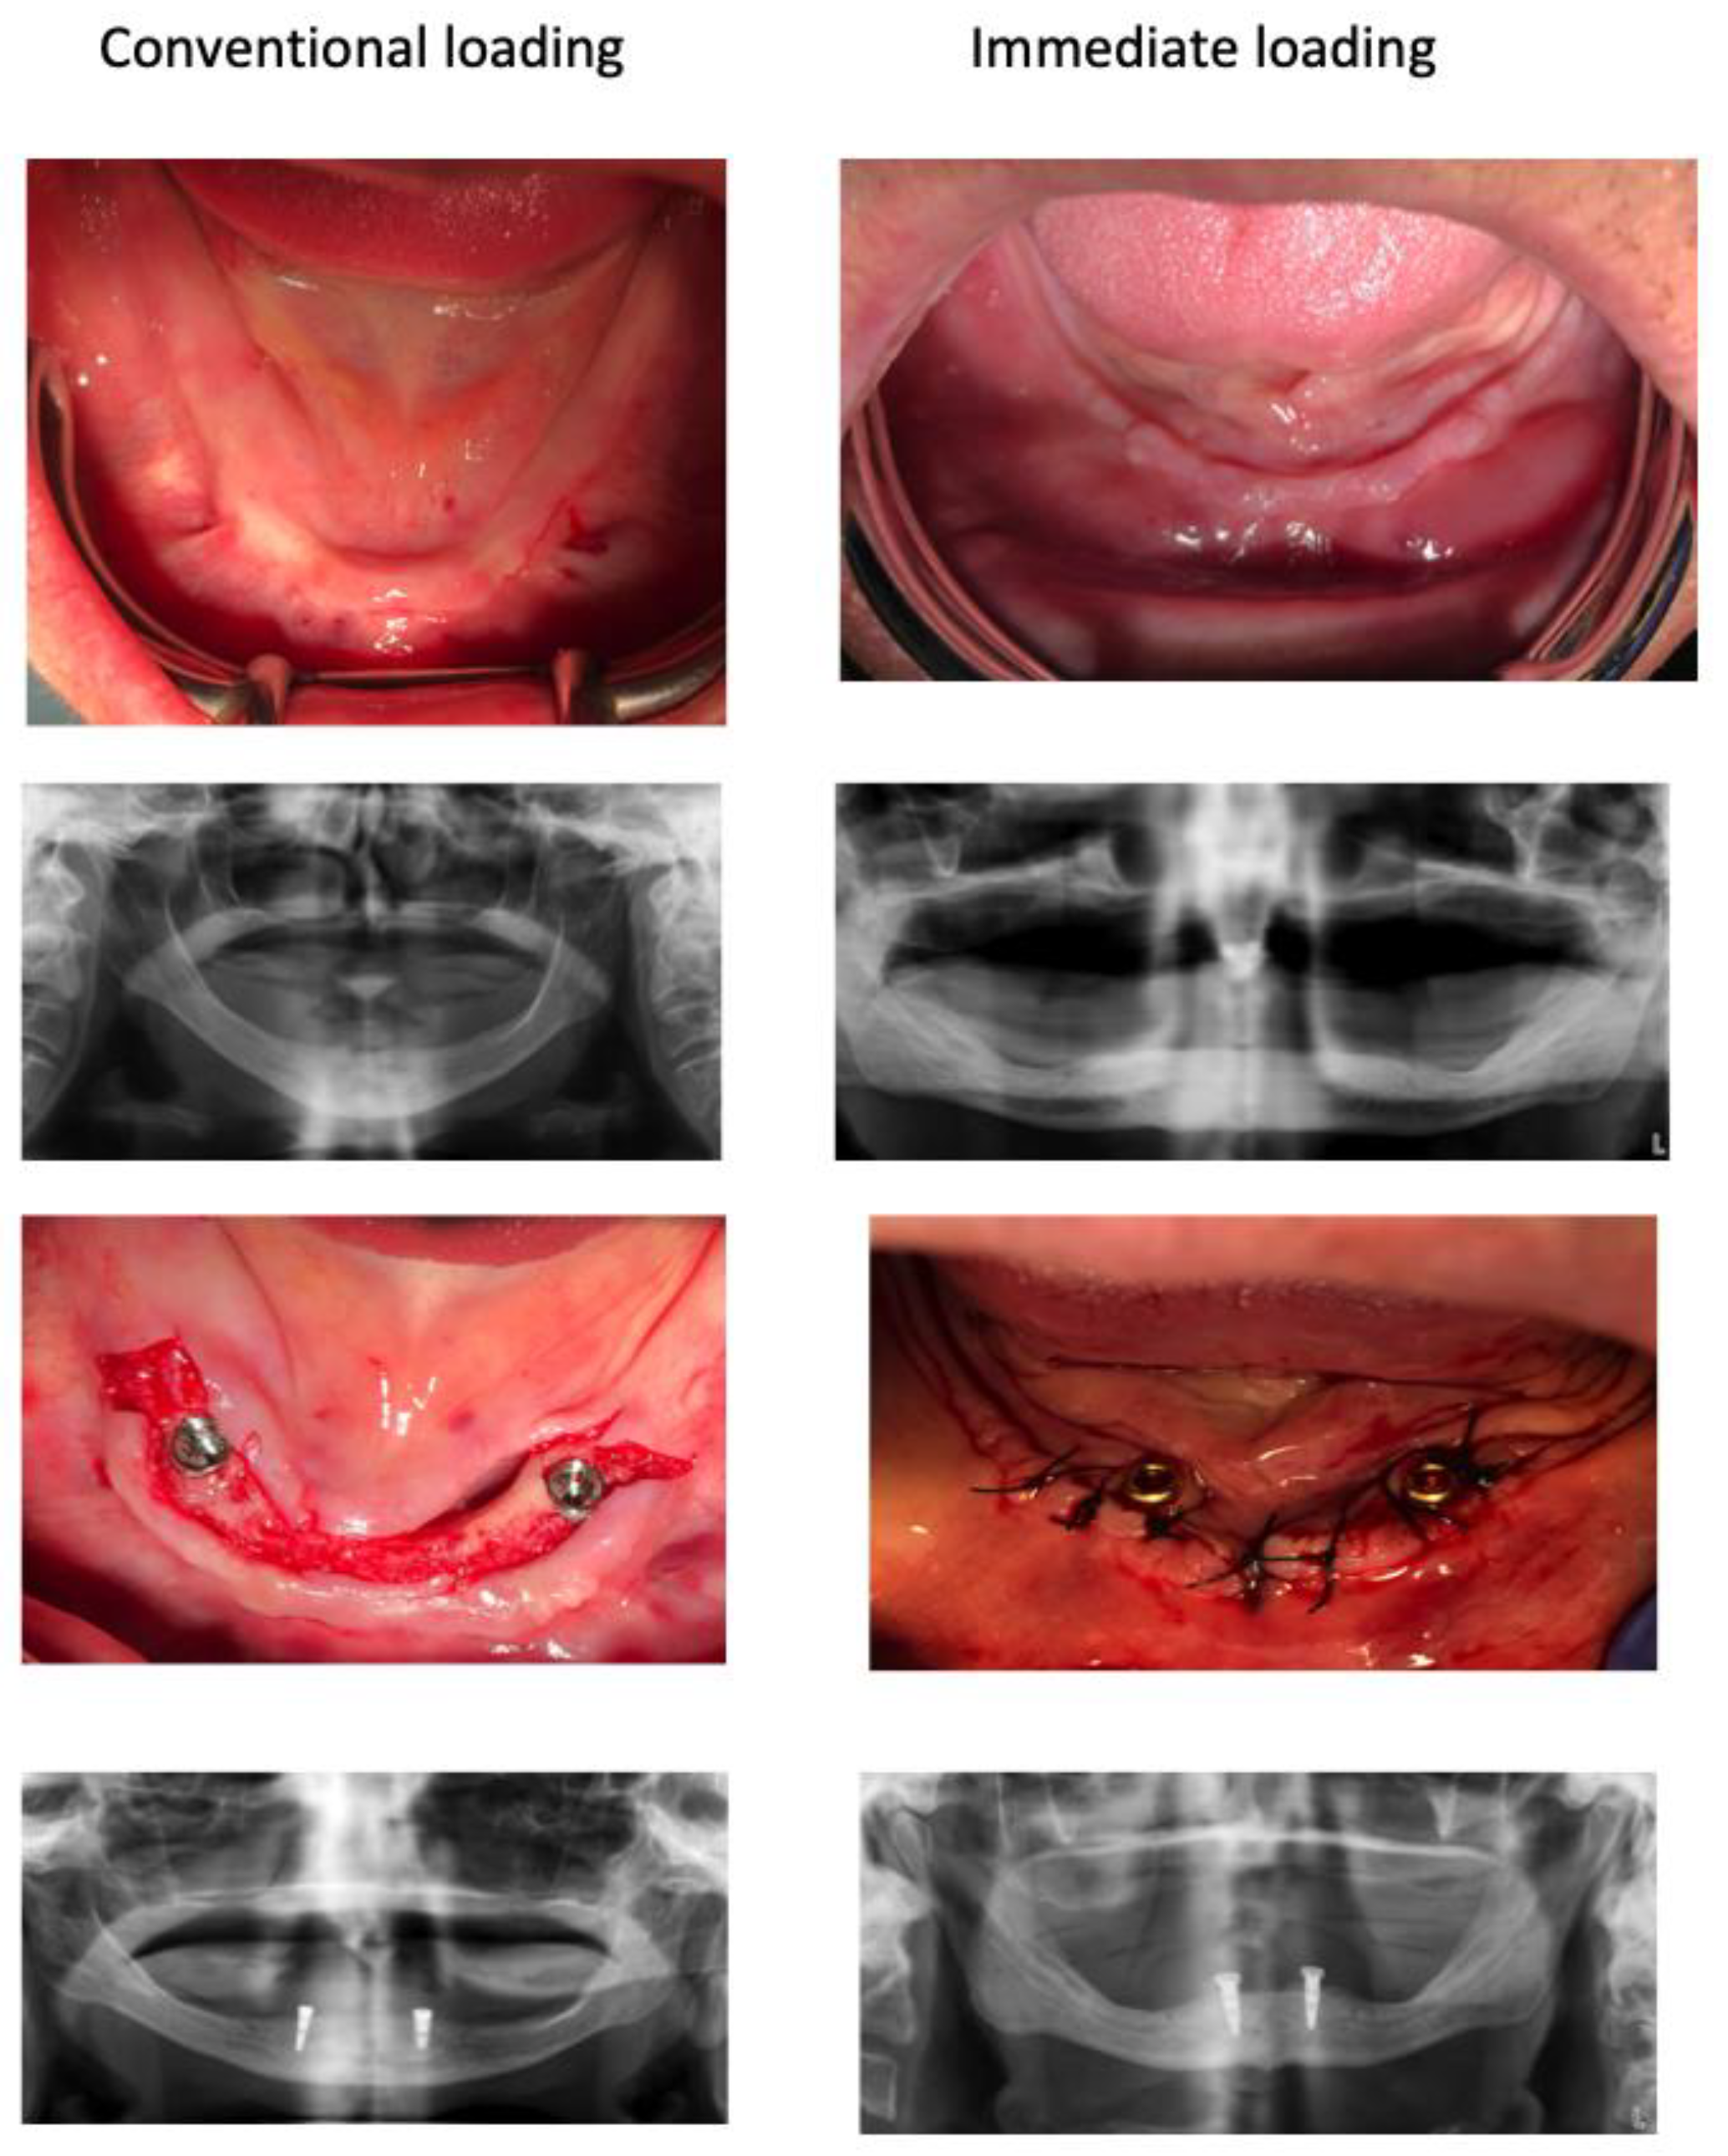

Figure 1.

Pre-operative and immediate post-operative clinical and X-ray observations of a representative case of each group. After two months both groups were indistinguishable.

After implant placements, the implants received Locator®-like abutments named VulkanLoc® (immediate loading group) or healing abutments (conventional loading group) whose height permitted an extramucosal exposure of at least 3 mm in height to give a certain degree of geometric retention of overdentures. To connect the mandibular prostheses, ball-headed burrs mounted on a hand-piece were used to grind down the internal surface of the prosthesis in contact with the abutments in order to emplace the complementary part of the VulkanLoc® abutment with pink acrylic reliner (Kooliner GC, Kortrijk, Belgium) for the immediate loading group) or a silicon-based reliner to fit the contour to the healing abutment (GC Reline II soft, Kortrijk, Belgium) for the conventional loading group. The Teflon retention cap placed over the VulkanLoc® abutment in this first phase had the least retentive power (400 grs: black). The overdentures were checked for occlusion to be properly bibalanced. Following this, a panoramic X-ray was taken in all of the patients with their acrylic prostheses set at maximum intercuspidation in order to obtain a radiographic record of the immediate post-operative period and thus monitor the basal position of the bone crest with respect to the implants for calculating vertical bone loss at the end of the follow-up (as depicts Figure 1). At seven days, the sutures were removed and the presence of pain, inflammation or wound dehiscence was recorded by inspection and palpation of the zone. From this time onwards, all consultations motivated by problems were attended to and recorded by the same investigators as those who participated in the implant phase and new denture phase, recording the occurrence of any biological or prosthetic complication.